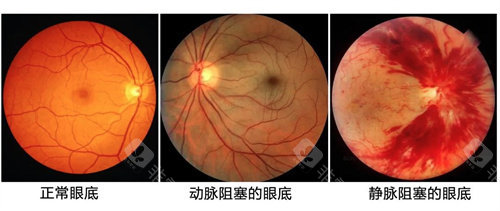

此外,还有眼底病、斜视与小儿眼科、眼整形等多个正规科室,多方面满足患者不同的眼科需求。

例如,某些医师在眼底病的治疗方面取得了重要突破,为众多患者带来了光明的希望。

科室引进了一系列较高的眼科检查和治疗设备,如光学相干断层扫描仪(OCT)、眼底荧光血管造影仪等,这些设备能够为医生提供比较准的诊断依据,帮助医生更精密地了解患者的病情。